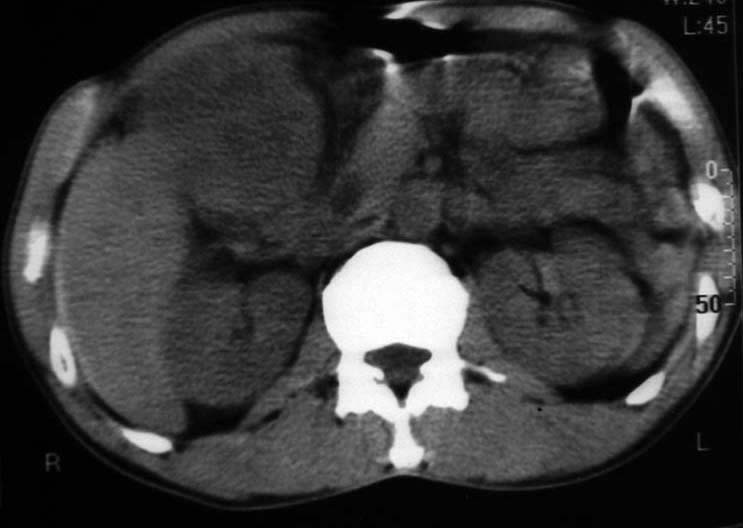

男,50y,右上腹包块痛10天,查:右上腹饱满,右肋下触及6*6cm大小包块,质硬,压痛。患者诉:10天前感冒胸闷,痛,后痛及右上腹部,既往有肝炎病史。

没有增强!只能考虑左叶内侧段巨块型肝癌(外生型)可能性大;胆囊呢?不除外胆囊癌累及肝脏。

病变位于胆囊窝内,其内密度不均,肝总管及胆总管扩张,胃里面没有清水充盈,不解为什么楼主不做好了准备再做呢,支持:“左叶内侧段巨块型肝癌(外生型)可能性大;不除外胆囊癌累及肝脏”建议增强吧。

考虑:肝左内叶巨块型癌,主动脉旁淋巴结转移.(有一层面似见胆囊受压.)